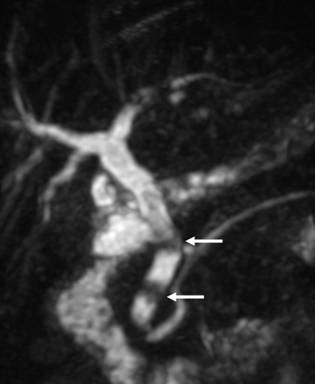

У %) больных при поступлении выявляли осложнения, сопутствующие механической желтухе (табл.2). Наиболее часто диагностировали печеночно-почечную недостаточность (15,79%) у пациентов с длительно существующей билиарной гипертензией и высокими цифрами билирубина, сопровождающуюся гемокоагуляционными расстройствами и энцефалопатией. Сопутствующий механической желтухе холангит, который диагностирован у,53%) больных, рассматривали как патологическое состояние, проявляющееся местным инфекционным воспалением желчных путей и системной воспалительной реакцией (СВР) с высоким риском перехода в билиарный сепсис [5]. При длительном существовании гнойного холангита у 7 (2,83%) пациентов выявлены холангиогенные абсцессы печени. Главной причиной их развития явились рубцовые стриктуры желчных протоков (Рис. 3) у 3 и длительно существующий холедохолитиаз (Рис. 4) у 4 пациентов. Одним из наиболее опасных осложнений механической желтухи, требующих экстренных хирургических манипуляций, считаем билиарный панкреатит, выявленный у,74%) пациентов, причиной развития которого являлся ущемленный камень БДС и спазм или стеноз сфинктера Одди (Рис. 5). При опухолях БДС и стойком нарушении оттока желчи билиарный панкреатит наблюдали лишь в 2 случаях (Рис. 6). Наиболее частыми признаками билиарного панкреатита были: боль, наличие интоксикационного синдрома с быстрым развитием гемодинамических расстройств. Желтуха при билиарном панкреатите носила, как правило, смешанный характер. [6,17].

Рис. 3 МРХПГ. Желчная гипертензия. Рубцовая стриктура проксимального отдела общего желчного протока.

Рис. 4 МРХПГ. Дефекты наполнения (конкременты) в просвете общего печеночного и общего желчного протоков.